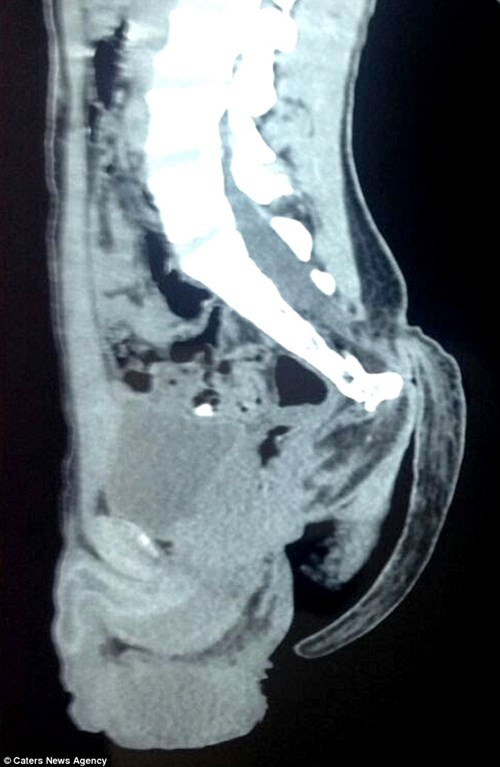

| Hình chụp Xquang chiếc đuôi. |